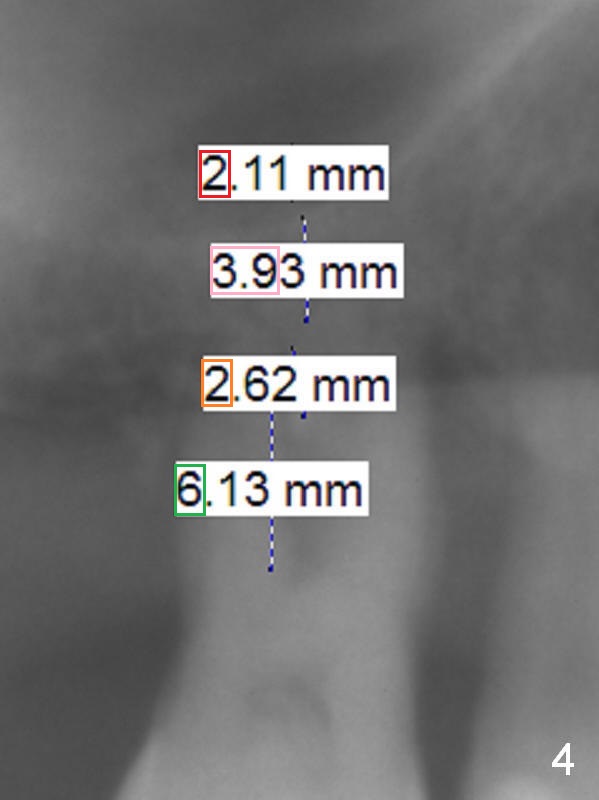

4 mm Bone, 6 mm Gingiva

A 44-year-old man requests an implant at #3 because of mobility. It appears that the bone height decreases from 6 mm (Fig.1,2: 3 years ago) to 4 mm (Fig.3,4, recently). After extraction and Clindamycin treatment, take PVS impression of the socket. Use initial drill with drill stopper of 3 mm and round burs with stoppers from 4 to 5 mm. If the buccal (B) and palatal (P) plate defect is severe, use a regular implant. Otherwise use an extra wide one. The advantage of the latter is length as short as 6 mm vs. 8 mm for the regular one. For the latter, 2 mm of the implant will be in the sinus (Fig.4 red box), 4 mm in bone (pink box) and 2 mm in the socket (orange box; to be surrounded by bone graft). Since the gingiva is 6 mm (Fig.4 green box), an abutment with 6 mm cuff should be chosen. To reduce occlusal interference, select abutment height 4 mm.